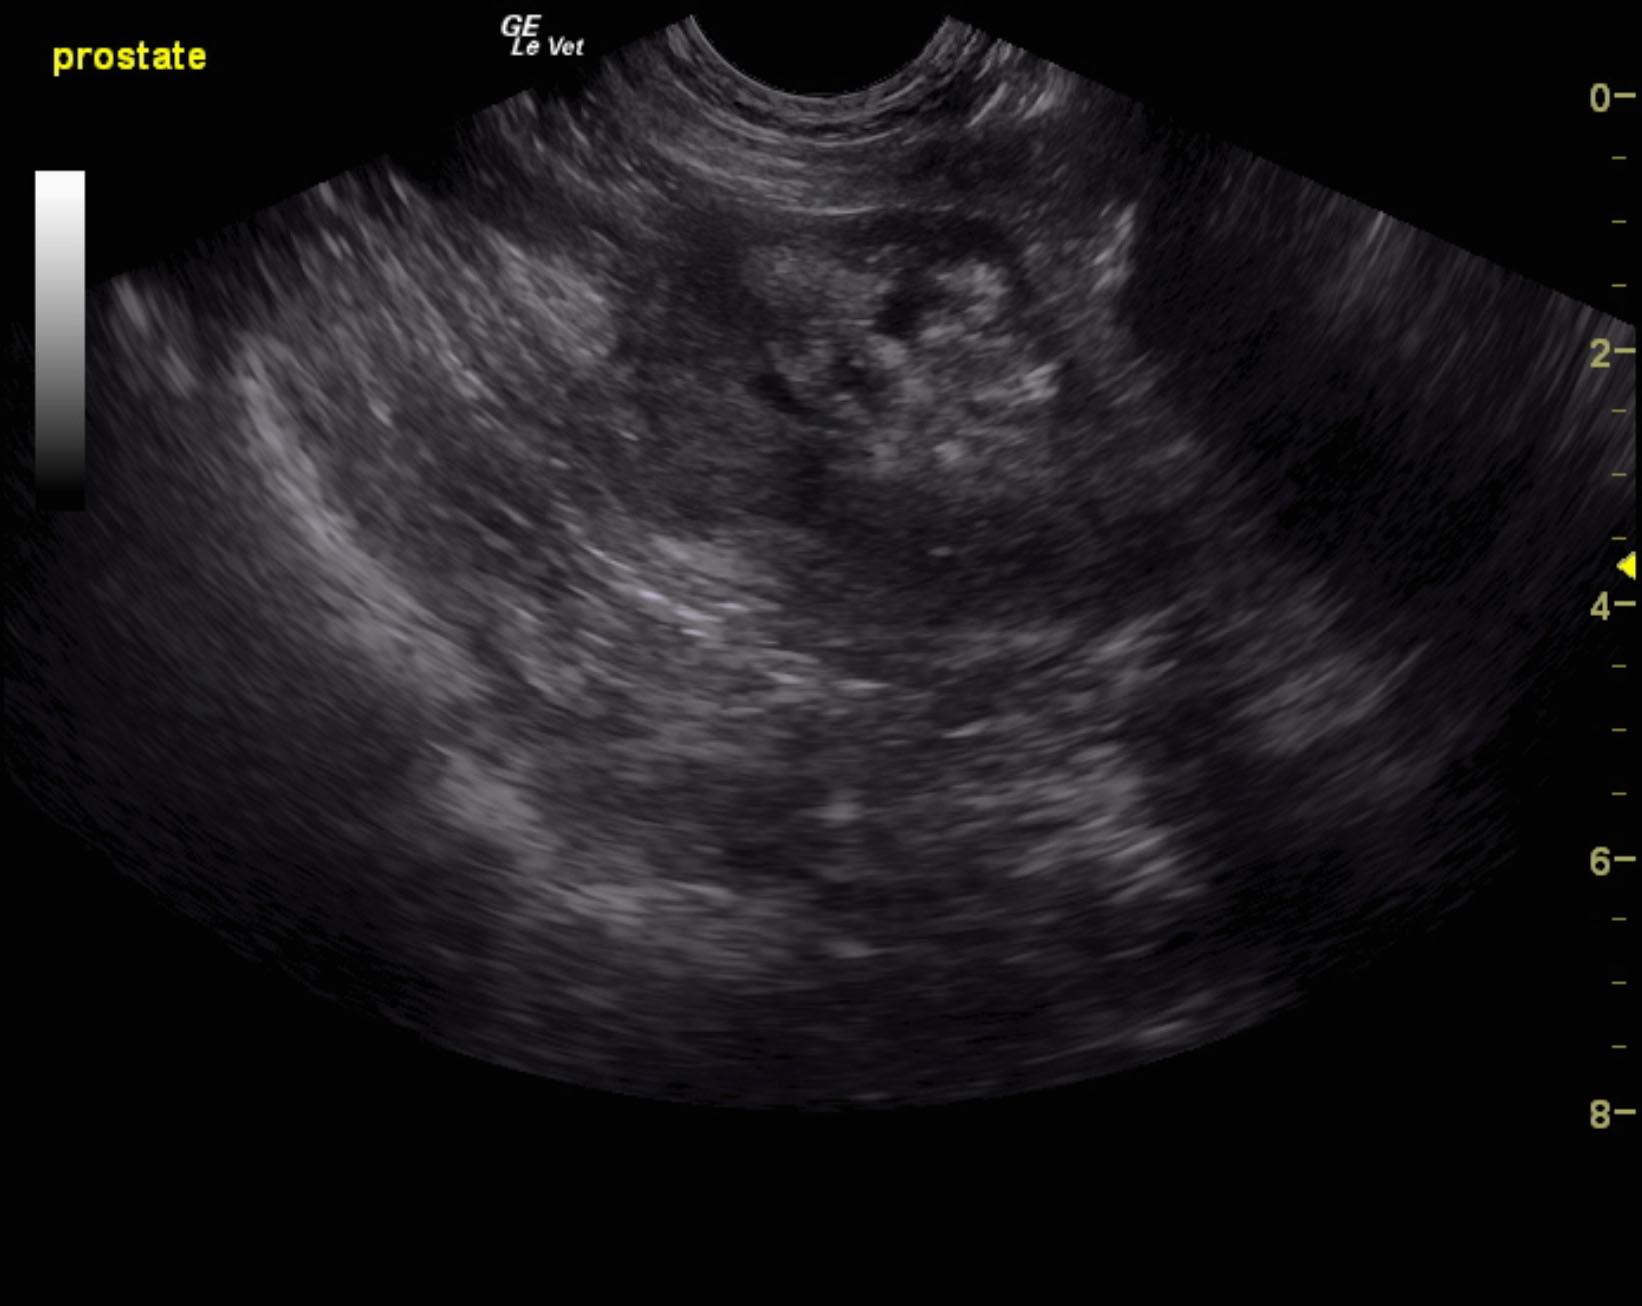

An 8-year-old neutered male mixed breed dog with a history of pollakiuria, stranguria, and weight loss. The dog was presented for evaluation of tenesmus, diarrhea, and hematuria. Physical examination and rectal palpation were within normal limits.